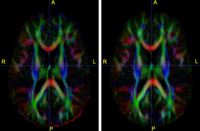

DTIregistration.png

A Framework for Joint Analysis of Structural and Diffusion MRI

We have developed a variational image-based approach to correct the susceptibility artifacts in the alignment of diffusion weighted and structural MRI.The correction is formulated as an optimization of a penalty that captures the intensity difference between the jacobian corrected EPI baseline images and a corresponding T2-weighted structural image.

New: Ran Tao, P. Thomas Fletcher, Ross T. Whitaker, in MICCAI 2008 on Computational Diffusion MRI.